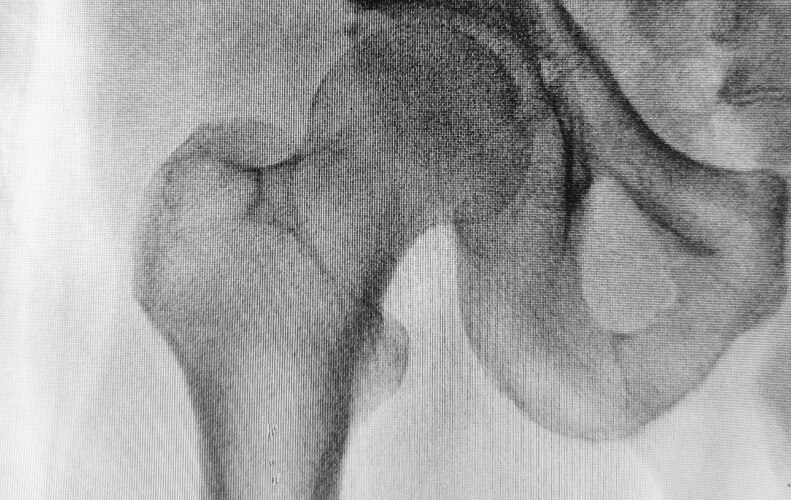

골다공증은 뼈가 약해지고 부서지기 쉬운 상태로 변하는 것입니다. 말 그대로 뼈의 밀도가 떨어져 빈 곳이 많아지는 겁니다. 특히 나이를 먹을 수록 골다골증에 의한 골절 가능성이 높아 위험합니다. 그리고 여성이 남성보다 골다공증 발병 가능성이 상대적으로 높습니다. 오늘은 골다공증의 원인, 치료 및 예방 전략에 대해 알아보겠습니다.

가장 일반적인 골다공증의 원인은 노화입니다. 나이를 먹을 수록 뼈의 밀도가 낮아져 약해진다는 것은 상식입니다. 특히 나이가 든 여성이 더 취약합니다. 여성은 특히 에스트로겐 수치가 감소하는 폐경 후 남성보다 골다공증 발생할 가능성이 더 높습니다. 유전적인 요인도 있습니다. 골다공증은 가족력이 있으면 쉽게 발병하는 경향이 있습니다. 라이프스타일은 건강을 좌우하는 중요한 요소입니다. 잘못된 식습관, 운동 부족, 흡연 및 과도한 음주는 모두 뼈 건강에 치명적인 영향을 미칩니다. 골다공증의 위험을 높이는 특정 병증도 있습니다. 갑상선 기능 항진증, 류마티스 관절염, 셀리악병 환자는 골다공증 발병 위험이 상대적으로 높습니다.